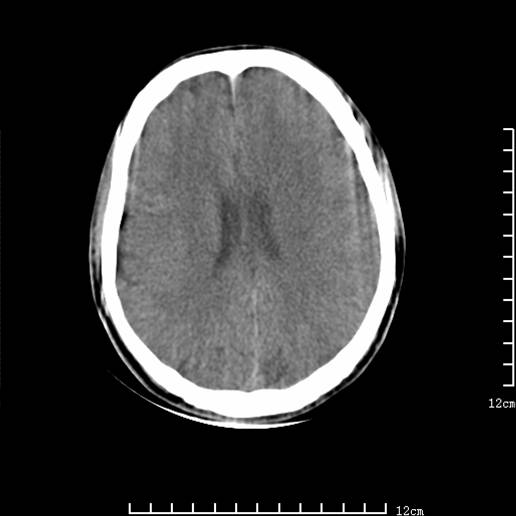

以下图像分别是3月25日凌晨及下午图像、3月27日、4月16日的ct图像。

3月25日下午

1)左侧额颞顶叶、岛叶及基底节区(相当于左侧大脑中动脉供血区)大面积脑梗塞。2)右侧基底节区腔隙性脑梗塞。

大脑中动脉供血区大面积脑梗塞没有问题。

支持左侧大脑中动脉分布区脑梗塞。